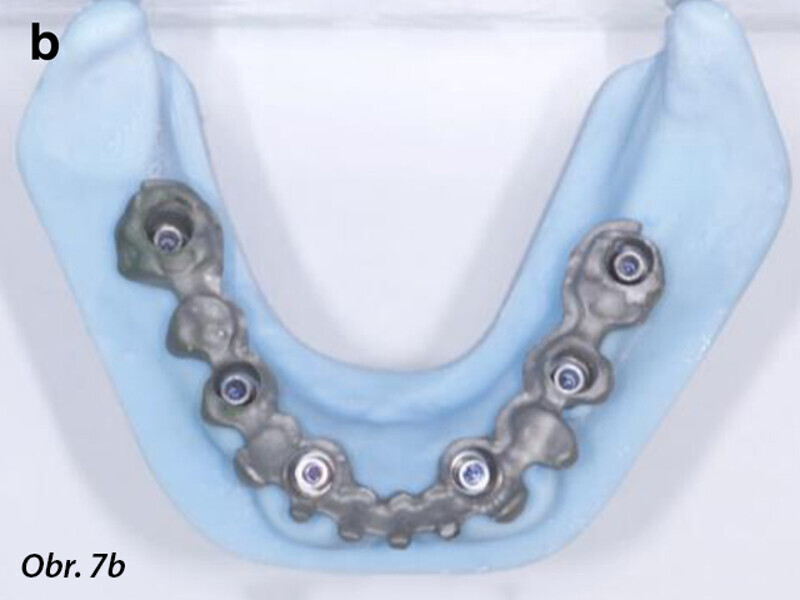

Počítačem asistované, šablonou se řídící okamžité zavedení a zatížení implantátu v dolní čelisti